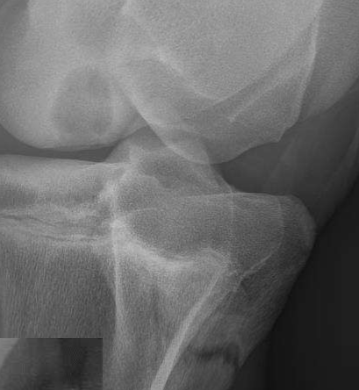

Fascial plane. Cranial is infrapatellar fat pad. Caudal fascial plane

Fascial planes

Which is abnormal and why?

Right because infrapatellar fat pad is indented and caudal fascial plane is obstructed